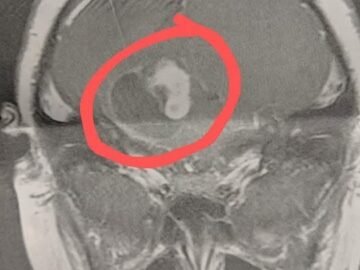

Meet Klara! She just turned 2 years old. Shortly after her birthday, her parents found a hard bump on her belly and quickly took her...